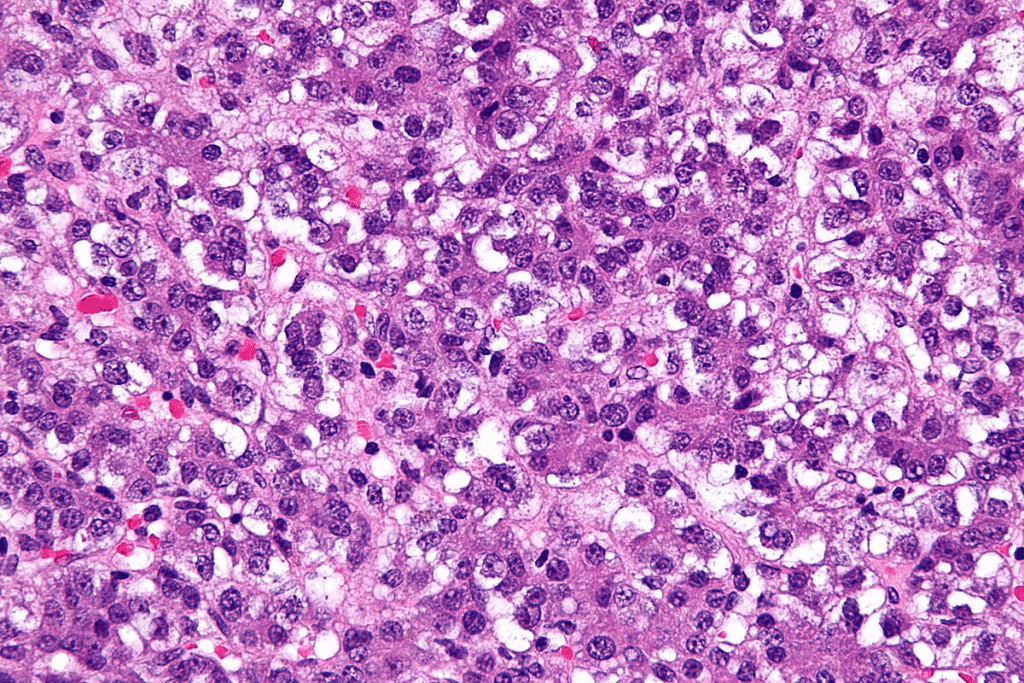

Biopsy Techniques and Considerations

Biopsy is the best way to confirm liver tumor diagnosis, by looking at tissue samples. There are many biopsy methods, like needle, laparoscopic, and surgical biopsies. The choice depends on the tumor’s location, size, and the patient’s health.

Biopsy techniques are chosen to get enough tissue for diagnosis safely. The tissue exam confirms the diagnosis and helps decide the best treatment.